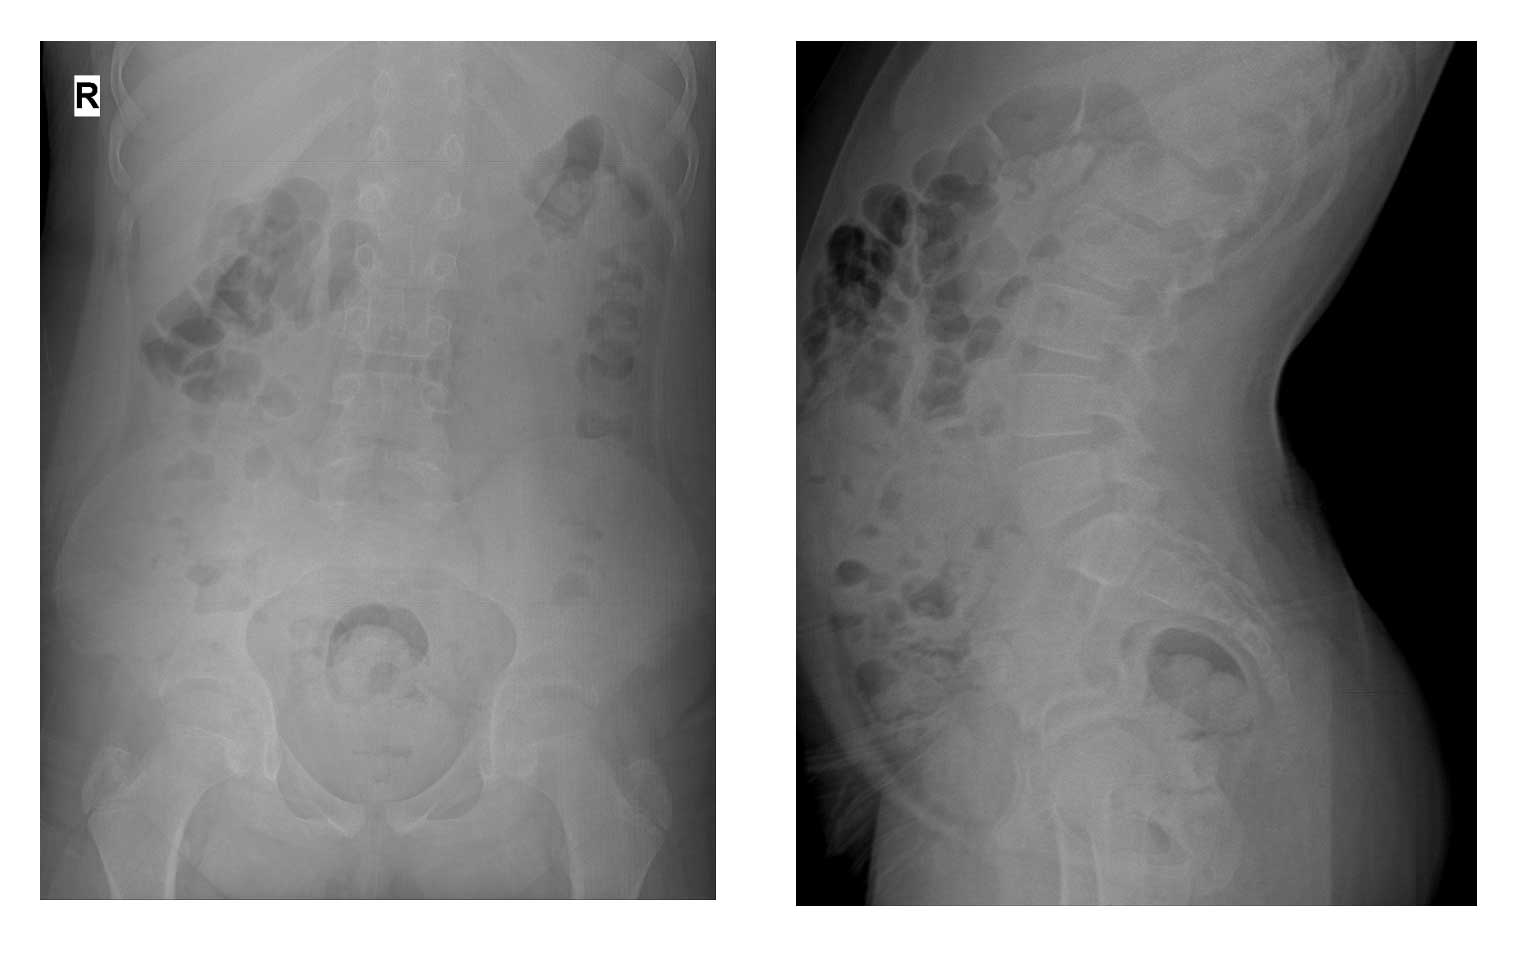

Ameliyat Öncesi: Röntgende özellik yok.